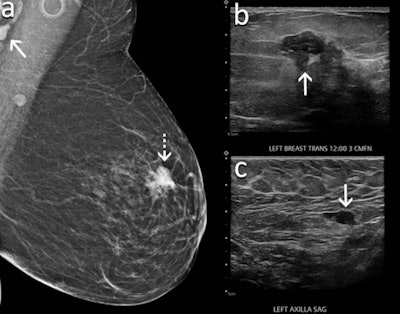

It's become known among radiologists that lymph nodes become swollen in women presenting for breast cancer screening as a side effect of the COVID-19 vaccine, regardless of vaccine brand. However, radiologists are challenged by this since lymphadenopathy occurring on one side of the body may also point to cancer.

Meanwhile, 823 women (68%) had screening exams and 334 patients had mammography and sonography performed the same day. Researchers found that out of these, mammography alone identified 29 cases (9%) of lymphadenopathy. Ultrasound alone identified 203 cases (61%) and both exams identified 102 cases (30%).

Lymphadenopathy was seen as early as one day following the first vaccine dose and as late as 71 days following the second dose. The average lymph node size was 1.8 cm.

Four patients were diagnosed with metastatic breast cancer, all of whom had suspicious concurrent mammographic findings in the breast on the same side of the body where the vaccine was given. Four other women were diagnosed with lymphoma, and one patient with a known history of lung cancer was diagnosed with lung cancer metastatic to an axillary lymph node.